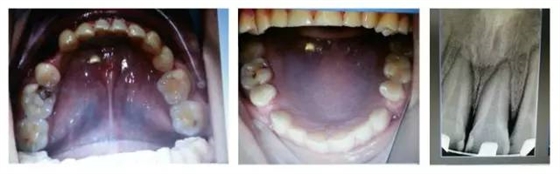

口內(nèi)情況,如以下照片所示:

您是否首先會想到,患者的牙齒是受外力撞擊引起的牙周膜急性創(chuàng)傷?或是(牙合)創(chuàng)傷引起?如果是創(chuàng)傷,這種創(chuàng)傷是如何形成的呢?權老師提示一,患者并無外傷史,進食很小心;提示二,從口內(nèi)照片可得知患者前牙無接觸,(牙合)創(chuàng)傷從何而來呢?

群里多位同仁已經(jīng)發(fā)現(xiàn)了它的不和諧之處,劉坦,劉曉強等多位醫(yī)生先后發(fā)現(xiàn):患者前伸(牙合)后牙有干擾。其他同仁也同時提出或需要進行適當?shù)恼{(diào)(牙合),或使用后牙(牙合)墊抬高后牙咬合,方能解決急性創(chuàng)傷。仔細看口內(nèi)的照片,從咬合的觀點和理論角度出發(fā),您捕捉到什么信息了嗎?

由上圖可知,患者全口牙齒磨耗較重,尖牙牙尖磨耗,無法起到引導和保護作用,上前牙牙根短,上中切牙腭側面邊緣嵴消失,

由此推斷:尖牙牙尖磨耗,患者在前伸(牙合)運動時,引導不足,前牙的接觸面過大,受力較大;患者在側方(牙合)運動時下前牙沒有了引導,會直接對側切牙造成撞擊;再加上前牙根較短,無法耐受,引起(牙合)創(chuàng)傷,繼發(fā)牙髓癥狀;失去尖牙保護(牙合),加重了牙齒的磨耗。